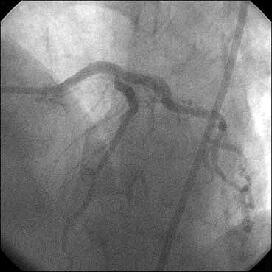

�Ǘ��72�Ώ����Brisk factor��HT, HL, DM�ł��B

��2�T�ԑO�̔��ǂƎv����Recent MI�ł��BLAD#7: total��Tristar3.0�~18?�����

�܂����B

����LCx ostium: 75%�ł��B������PCI���悤�Ǝv���̂ł����A�ǂ̂悤��strategy

���l������ł��傤���H

�����ł��B

�Y�t���ꂽ�A���W�I�̂����A�ŏ��̂��̂�q������ƁALCx�������ɂ���Ȃ�́g��

�肵��h�́A�����悤�ł��B

DCA����������̎�i�ł����ACB���X�e���g�ł����܂�Ȃ��̂ł͂Ȃ��ł��傤

���B

�������A�ł��邾���X�e���g�̃T�C�Y��傫���������̂ŁAIVUS���������ł����A

LAD��������plaque shift���N���A�ň�LMT�ł�kissing�̉\��������̂ŁA

�K�C�h��7Fr�iradial���ׂ����TFI�Łj�A�X�e���g�A�����݂ɍۂ��ẮA

�O�̂��߁ALMT��LAD��protect wire�A�Ƃ������Ǝv���܂��B

����������������������������������������������������������������������������